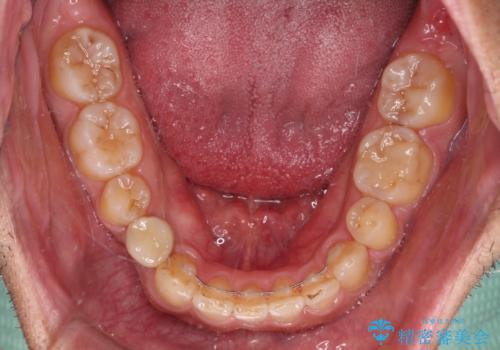

- 上下前歯のデコボコと下顎小臼歯の欠損によるスペースを気にして来院された患者様です。

下顎は左右1本ずつ小臼歯が欠損しており、右側にはやや大きな欠損がありました。

欠損により下顎歯列は相対的に小さく、上顎に深く咬みこんでしまうディープバイトとなっていました。

インビザラインによる治療を希望されたため、左側のスペースは閉じ、右側はスペースをより拡大し、インプラント補綴を行うこととしました。

咬合力が強く、インビザラインのみではディープバイトを改善することができず、半年間ほどワイヤー装置による矯正治療を行いました。

インプラントの埋入は矯正治療中に行い、矯正治療後はインプラント上補綴および、前歯のセラミック治療を行いました。